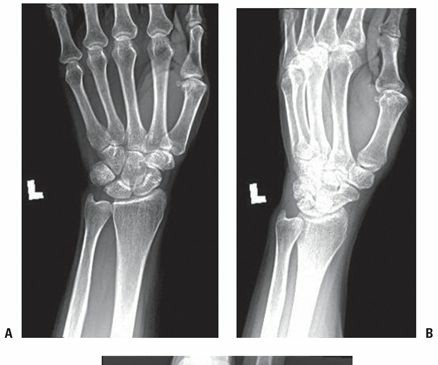

DISTAL RADIUS FRACTURES EPIDEMIOLOGY Distal radius fractures are among the most common fractures of the upper…